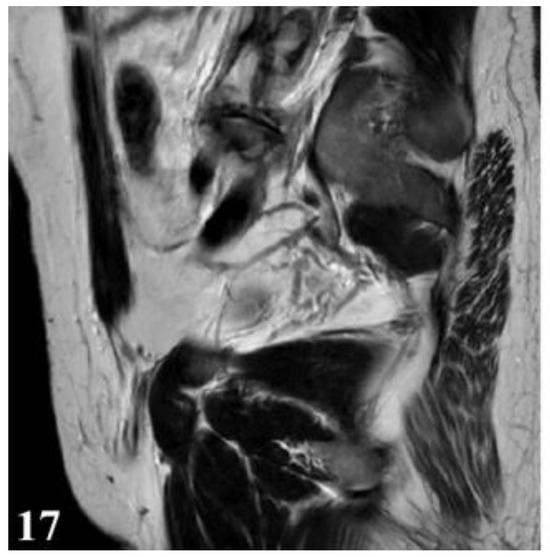

Considering the impossibility of performing an ideal cystectomy, it was decided to perform an efficient drainage by closing the remaining retroperitoneal cavity after mounting a drain tube (through which the lavage and drainage slope at the base of the left thigh with tubes passed through the muscle gap is carried out). Adjacent peritoneal drainage and anatomical parietorrhaphy. Native MRI examination and post-operative intravenous post-contrast (Figure 17 and Figure 18), reveals: diffuse infiltrative-edematous appearance at the level of the iliopsoas muscle on the left side, with the presence of a collection with peripheral type gadophilia, difficult to appreciate under dimensional ratio, with a tendency to diffuse extension, developed predominantly intramuscularly at the level of the psoas muscle on the left side, with the predominant interest of its peripheral portion between 7–3 o’clock (being tangent to the external iliac vessels on the left side, with present, homogeneous flow at their level), extended to at the level of the ipsilateral iliac muscle and later in a caudal direction at the level of the iliopsoas muscle on the left side up to the vicinity of its distal insertion, after which it insinuates between the muscles of the antero-internal region of the thigh on the left side up to the border between the proximal third and the middle third of the thigh, and coming into contact on several sections with the femoral vessels on the left side, but without causing changes in caliber or flow at their level. At the level of the proximal portion there is a fistulous tract with a maximum thickness of approximately 0.7 cm, externalized at the level of the root of the left thigh in the antero-internal region which seems to communicate in depth with the previously described collection. In the proximal portion of the thigh on the left side, diffuse infiltrative-edematous changes adjacent to the previously described collection are evident at the level of the intermuscular space in the anterior region of the thigh, without being accompanied by similar changes at the level of the muscles in the anterior region of the thigh (Figure 17 and Figure 18).

Figure 17.

T2W sequence, sagittal—Postoperative residual hydatid cyst located at the level of the left iliopsoas muscle and deep to the left gluteus maximus muscle (part 1).

Figure 18.

T2W sequence, sagittal—Postoperative residual hydatid cyst located at the level of the left iliopsoas muscle and deep to the left gluteus maximus muscle (part 2).

Deep from the gluteus maximus muscle on the left side, there are multiloculated, multiple septate intralesional, relatively well delimited areas, which seem to communicate both with each other and with lesions of a similar appearance located in the thickness and adjacent to the quadratus femoris muscle on the left side, with total dimensions in the coronal plane of approximately 11.3/6.4 cm, with the most likely appearance of parasitic cysts (Figure 19, Figure 20 and Figure 21).